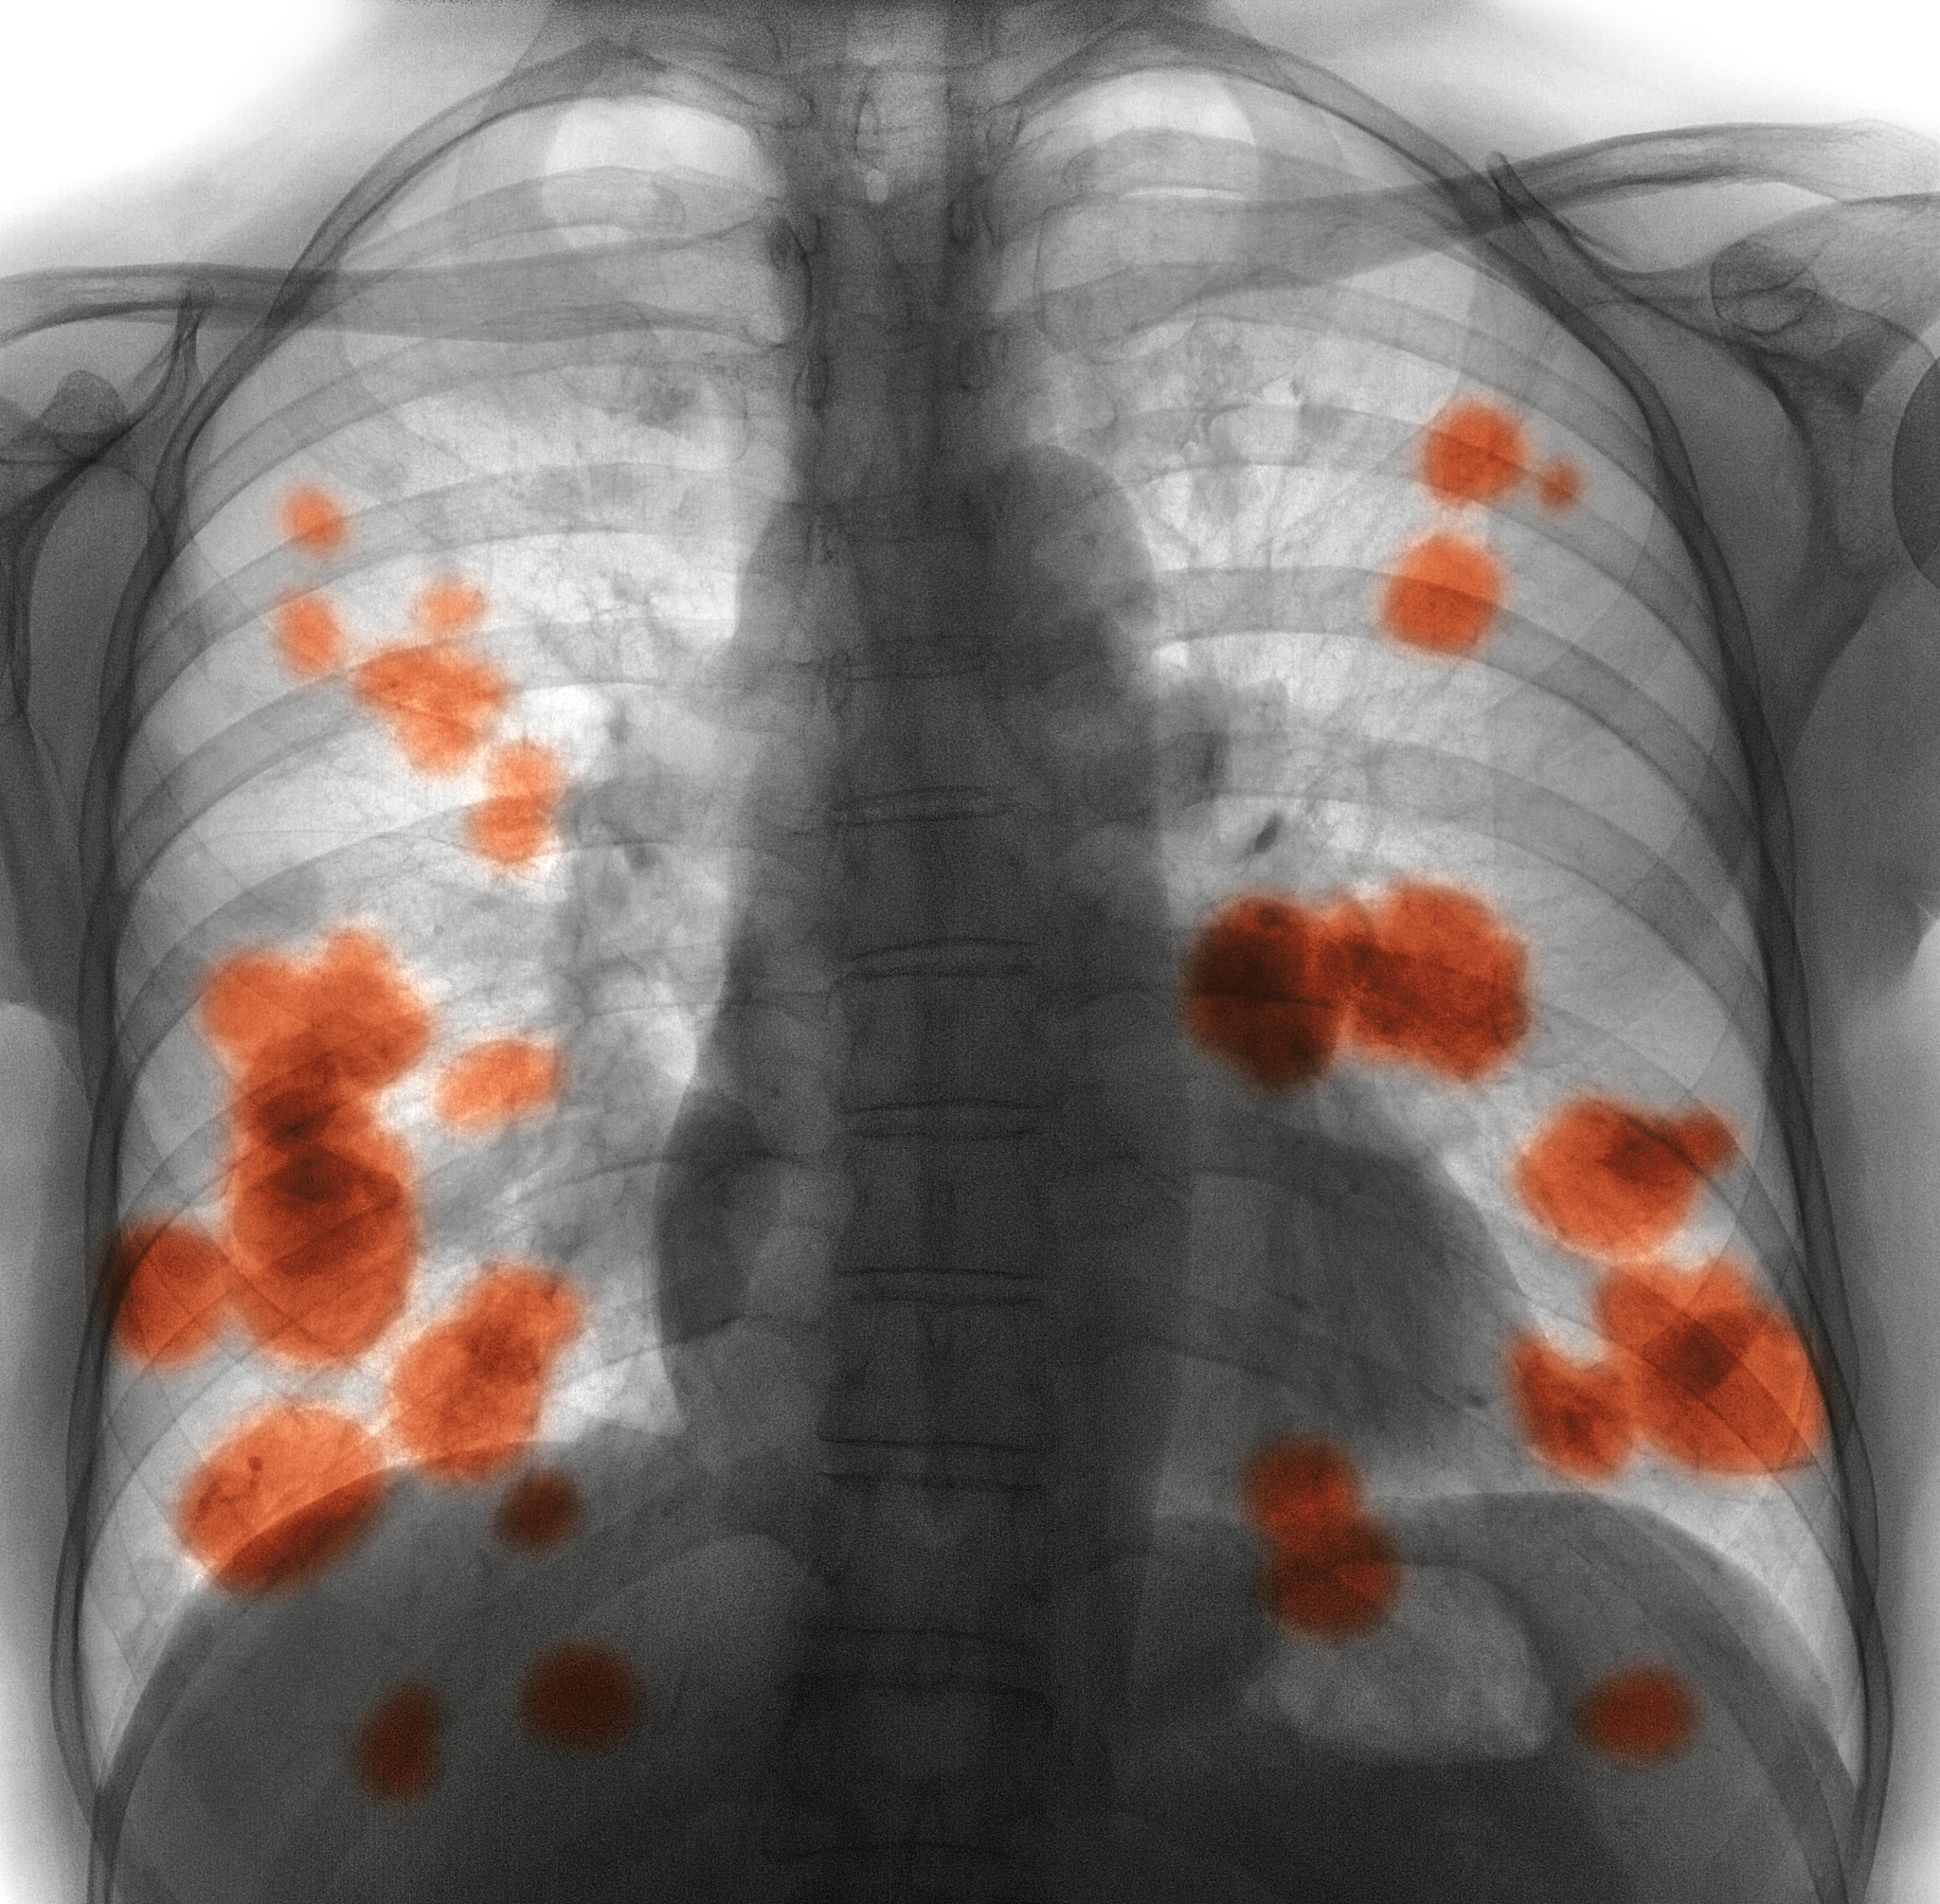

右肺腺癌术后呼吸衰竭伴肌肉脓肿感染护理指南

右肺腺癌术后出现呼吸衰竭和肌肉脓肿感染是较为严重的并发症,需要进行积极的治疗和护理。本文将为患者家属和护理人员提供详细的护理指南。